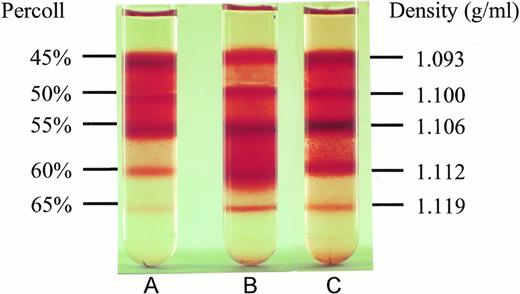

To test whether NAC might affect SS erythrocyte dehydration, we isolated light density SS RBCs and incubated them at 37°C under cyclic deoxygenation-reoxygenation for 16 hours plus (Fig 2C) or minus (Fig 2B) 20 mmol/L NAC. The control represents LDSS erythrocytes, which were incubated at 37°C for 16 hours minus NAC and without cycling (Fig2A). As shown in Fig 2 and Table 3, in vitro cycling of LDSS erythrocytes causes a large conversion to high density SS erythrocytes. NAC (20 mmol/L) partially blocks this conversion causing statistically significant decreases in the percent RBCs found in the 60% Percoll layer (density = 1.112 g/mL) and increases in the percent RBCs found at lower density (45% and 50% Percoll layers, density = 1.093 and 1.100 g/mL) (Table 3). There was no statistically significant difference in the percent ISCs found at any Percoll layer ± 20 mmol/L NAC. This means that decreases in ISCs found in whole blood smears from NAC-treated cycled cells (Table 2) was accompanied by NAC blocking the formation of high density SS cells in vitro (Table 3), which contain the highest percent ISCs.

Effect of NAC on SS erythrocyte density. Low density SS erythrocytes that were incubated at 37°C for 16 hours without cycling or NAC (A), with cycling, but without NAC (B), and with cycling in the presence of 20 mmol/L NAC (C), were placed on Percoll gradients (45% to 65%) and centrifuged at 907g for 45 minutes. Note NAC's ability to inhibit dense cell formation. Density of the RBCs in different Percoll layers was obtained by sedimenting density marker beads (Pharmacia, Piscataway, NJ) under identical conditions.

Effect of NAC on SS erythrocyte density. Low density SS erythrocytes that were incubated at 37°C for 16 hours without cycling or NAC (A), with cycling, but without NAC (B), and with cycling in the presence of 20 mmol/L NAC (C), were placed on Percoll gradients (45% to 65%) and centrifuged at 907g for 45 minutes. Note NAC's ability to inhibit dense cell formation. Density of the RBCs in different Percoll layers was obtained by sedimenting density marker beads (Pharmacia, Piscataway, NJ) under identical conditions.